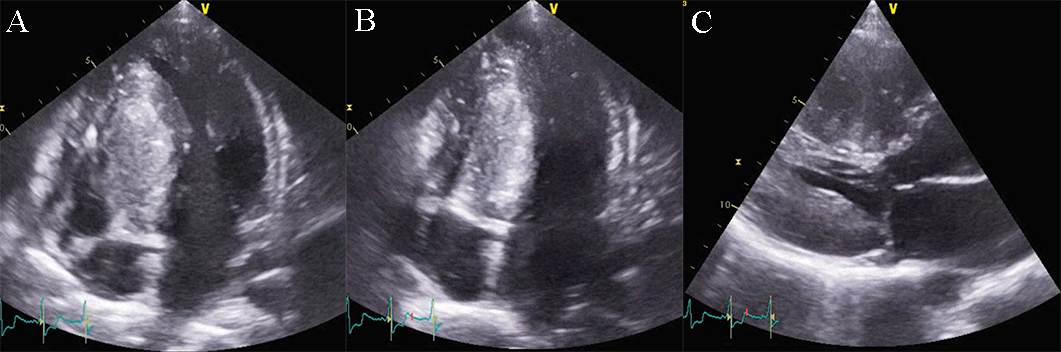

Arrhythmogenic cardiomyopathy (AC) is defined by fibrous and fibro-fatty replacement especially of the RV myocardium, affecting the inflow and outflow tract, but also the apex. This process most commonly affects the posterior and inferior areas of the right ventricular inflow tract adjacent to the tricuspid valve, but it also affects the anterior infundibulum and the apex, thus forming what is known as the “triangle of dysplasia”. According to recent data, there is also involvement of the postero-lateral wall of the LV. In the LV the fibro-fatty replacement determines a transmural lesion but the process starts from the subepicardial to the subendocardial LV layers. It has been demonstrated that in left ACM, the scar tissue tends to localize in the inferolateral subepicardial LV wall. In the initial assessment of AC, these typical regional wall motion abnormalities may be detected. Later changes may involve the RV free wall and become global, producing RV dilation (Fig. 11 and Appendix Video 6). Echocardiography is the first line and sometimes a sufficient method of evaluation in patients with AC.

Fig. 11.Echocardiographic aspect of AC. Apical 4 chamber view showing dilation and thick right ventricular free wall. A video of the apical 4 chamber view is available online (Appendix Video 6).